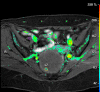

Methods: Semi-quantitative DCE MRI images of 71 indeterminate adnexal lesions were retrospectively reviewed. A region of interest was manually drawn onto the enhancing solid component, psoas muscle and normal outer myometrium. The DCE parameters were evaluated, and the lesion-to-internal-reference ratios were calculated.

Results: When the wash in rate of the lesion was higher than that of the myometrium, 97% specificity and 12% sensitivity for borderline/malignancy was reached. When the maximum relative enhancement and maximum absolute enhancement (SImax) of the lesion was less than those of the psoas, 100% specificity for benignity was achieved. The highest area under the curve (AUC) (0.807) was achieved using a SImax lesion-myometrium ratio. A slightly lower AUC (0.799) was achieved using a SImax lesion-psoas ratio, but the psoas muscle was more frequently measurable in the same slice as the lesion ROI. Although the AUC was higher, when using ratios instead of individual DCE values, this was not significantly different.